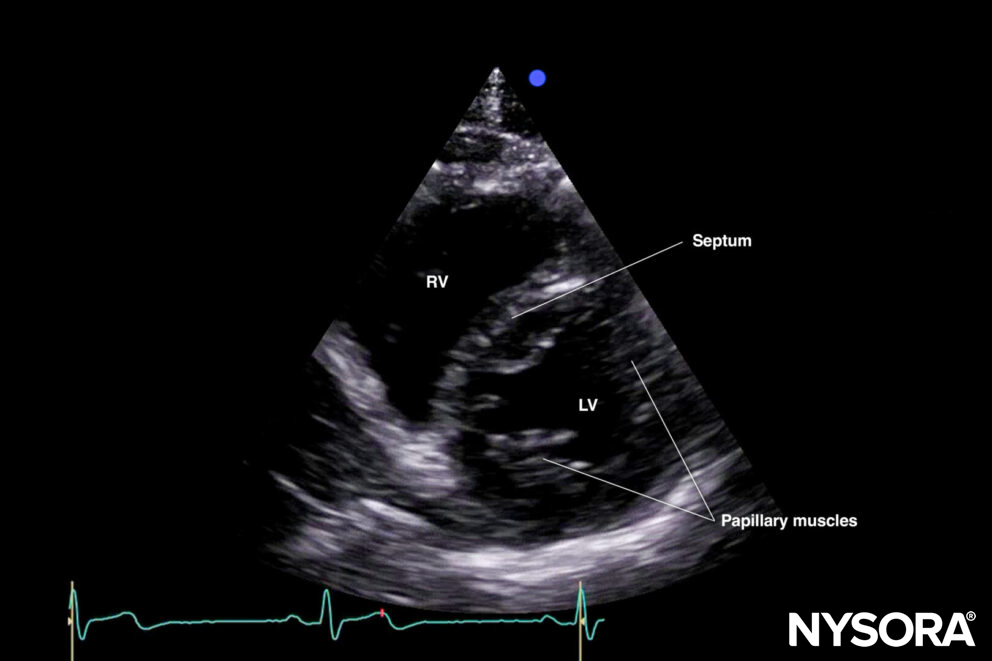

The standard parasternal short-axis view cuts the heart through the transverse plane.

Sonoanatomy of the heart in the parasternal short-axis view. Right ventricle (RV), septum, left ventricle (LV), and papillary muscles.

C. Papillary muscle level or standard parasternal short-axis view: Right ventricle, left ventricle, papillary muscles (posteromedial and anterolateral papillary muscle).